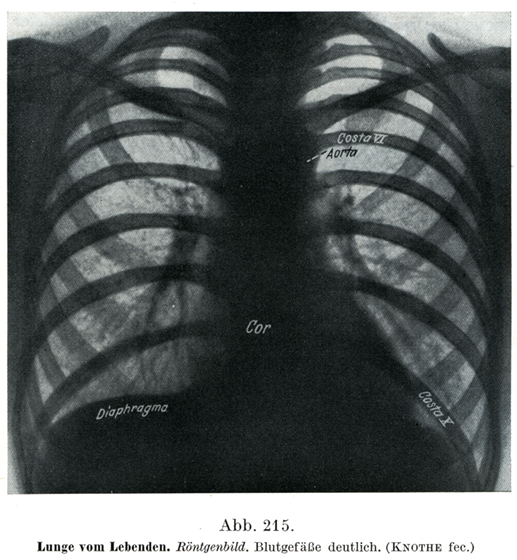

[図215]生体の肺 レントゲン像,血管が明かにみえる.